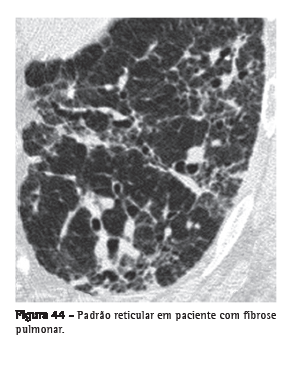

Padrão reticular

Alteração, usualmente relacionada às doenças intersticiais, caracterizada nas radiografias por inúmeras pequenas opacidades lineares que resultam em uma aparência de rede.(1) Na TCAR, é possível individualizar os componentes responsáveis por esse padrão na radiografia, que usualmente estão relacionados à presença de linhas intralobulares e septais (Figura 44) ou à presença de cistos cujas paredes se apresentam como linhas na radiografia, como nas doenças císticas pulmonares, no enfisema associado a bolhas e até mesmo nos cistos de faveolamento.(1,3,7)

Ver também Linhas intralobulares.